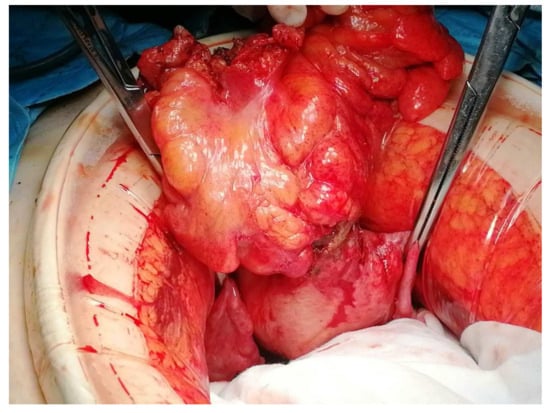

The treatment approach was discussed in a multidisciplinary team with the involvement of Gynaecology, Gastroenterology, General Surgery, Pathology, and Radiology. The patient underwent a programmed exploratory laparotomy via a midline incision which identified the sigmoid wall adherent to the uterine fundus with an approximately 3 cm extension; the uterus was normal in size and consistent with the small myomas identified; the adnexa were atrophic; and there were no adhesions or other abnormal findings. The procedure continued with en bloc colonic resection and primary anastomosis in the same operative time, total hysterectomy, and bilateral adnexectomy. Intraoperative frozen section examination revealed fibrous and unspecific inflammatory tissue without malignant aspects and, therefore, the procedure was finalized (Figure 3 and Figure 4).

Figure 3. Intraoperative findings showing the sigmoid colon adherent to the serosal surface of the uterine fundus with a fistulous communication between the two viscera.